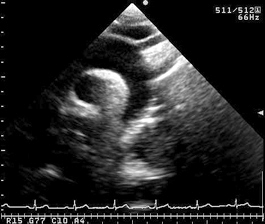

この断面は大動脈弓部から下行大動脈が描出され、大動脈解離の診断に有用である。

胸骨上窩に探触子を置き、短軸断面と同じ向きでビームを被検者の左足方向に傾けると得られる。